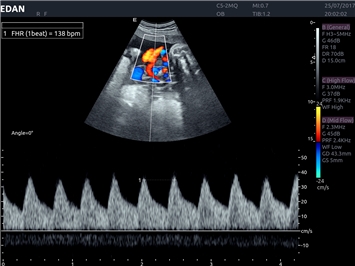

EDAN Acclarix LX4

Расширьте свои представления. Использование усовершенствованной платформой Acclarix система LX4 обеспечивает непревзойденную четкость изображений и интеллектуальный рабочий процесс для всех пользователей, являясь при этом наиболее экономичным решением.

EDAN Acclarix LX4 представляет собой инновационную ультразвуковую систему, построенную на усовершенствованной платформе Acclarix. Сочетание высокого качества визуализации с интеллектуальным рабочим процессом делает эту систему оптимальным выбором для клиник, ценящих эффективность и экономичность.

• Тканевая допплеровская визуализация (TDI)

Тканевой допплер:

Да

Цветовой допплер:

Импульсно-волновой допплер:

Триплексное сканирование: